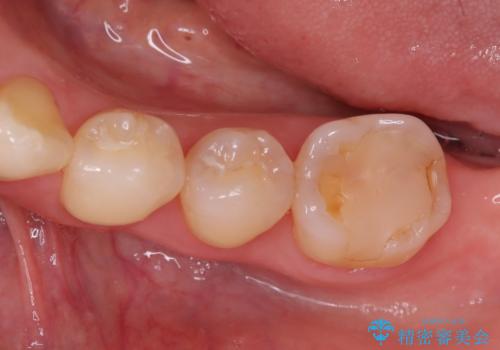

繰り返すプラスチックの欠けを解消。広範囲の修復に適したセラミッククラウン

担当医 河口智英